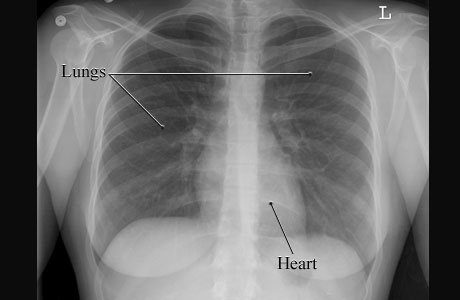

X-Ray of a Normal Chest

Image of a normal chest

Courtesy of Intermountain Medical Imaging, Boise, Idaho.

This is a picture of a normal chest X-ray of a woman showing the air-filled spaces of the lungs and the more solid gray shape of the heart. The lungs and heart are normal in size and shape.